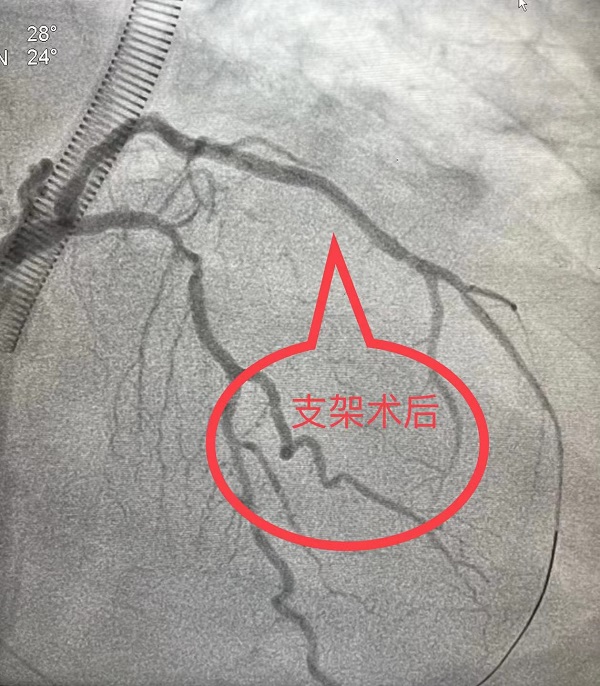

7月11日,潘女士在陕健医二一五医院胸外科进行腔镜下胸腺瘤手术,经过术后10天的恢复,7月21日8时,潘女士准备出院,而就在此时,潘女士突发意识丧失,呼吸心跳骤停,胸外科薛锋主任立即组织抢救,心电监护提示心室颤动,一场与死神赛跑的战斗展开,心肺复苏、电除颤、气管插管、呼吸机辅助呼吸……生命体征恢复,医院心内一科刘二伟主治医师急会诊,行心电图检查见Ⅰ、aVL、V4-V6导联ST段抬高型0.1mV–0.3mV,考虑急性ST段抬高型心肌梗死,刘积伦主任医师在气管插管下急诊行冠脉造影术,冠脉造影提示左旋支中段100%闭塞,急诊行冠脉支架植入术,顺利开通了急性闭塞的冠脉。术后,经过医生和护士精心治疗和护理,患者恢复良好,顺利康复出院。